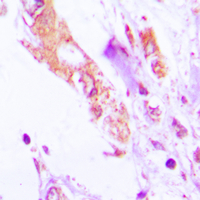

Immunohistochemical analysis of IL-1 beta staining in human lung cancer formalin fixed paraffin embedded tissue section. The section was pre-treated using heat mediated antigen retrieval with sodium citrate buffer (pH 6.0). The section was then incubated with the antibody at room temperature and detected using an HRP conjugated compact polymer system. DAB was used as the chromogen. The section was then counterstained with haematoxylin and mounted with DPX.